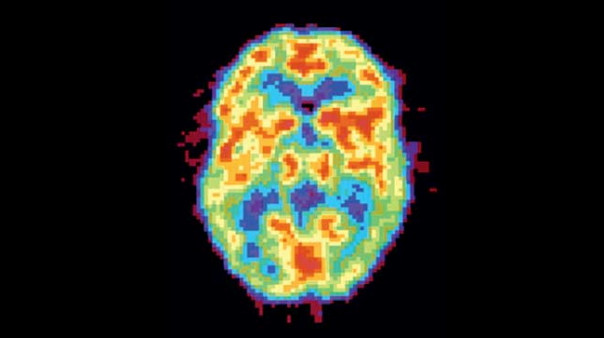

Активность мозга сильно различается не только во время бодрствования и сна — есть множество промежуточных состояний, которые можно различить во время позитронно-эмиссионной томографии.

НЕСПЯЩИЙ МОЗГ. Активность мозга в этой стадии (красные зоны на снимке) похожа на то, что происходит в REM-сне